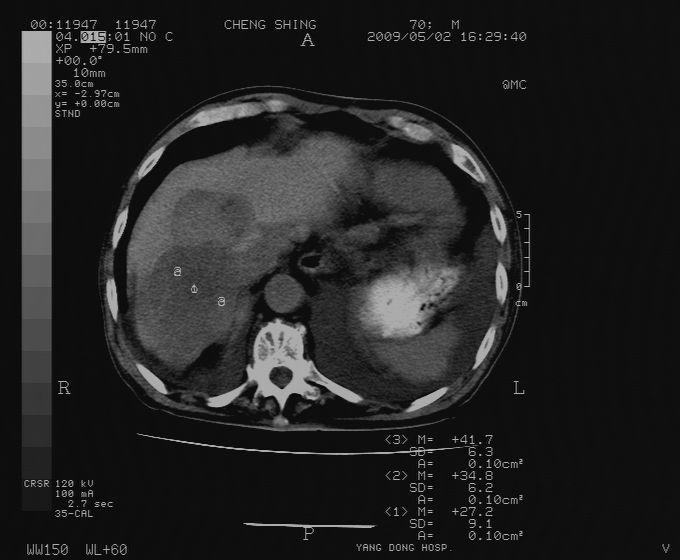

标题: CT19743:男70岁,肺部疾病入院,B超发现肝右叶占位,CT [打印本页]

标题: CT19743:男70岁,肺部疾病入院,B超发现肝右叶占位,CT

肝表面塌陷,病灶周围有子灶,前面较大子灶强化符合肝癌表现,考虑肝癌肝转移可能性大.

2.两侧胸水,左下肺不张!

1)考虑肝癌并肝内转移。2)少量腹水。3)双侧胸腔积液。

1)考虑肝癌并肝内转移。2)少量腹水及双侧胸腔积液。3)椎体退变。